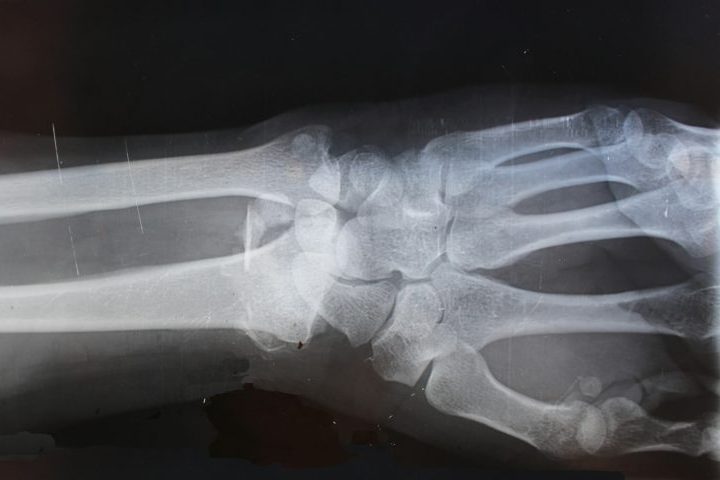

Com condição de saúde rara, homem tem ossos mais resistentes que granito